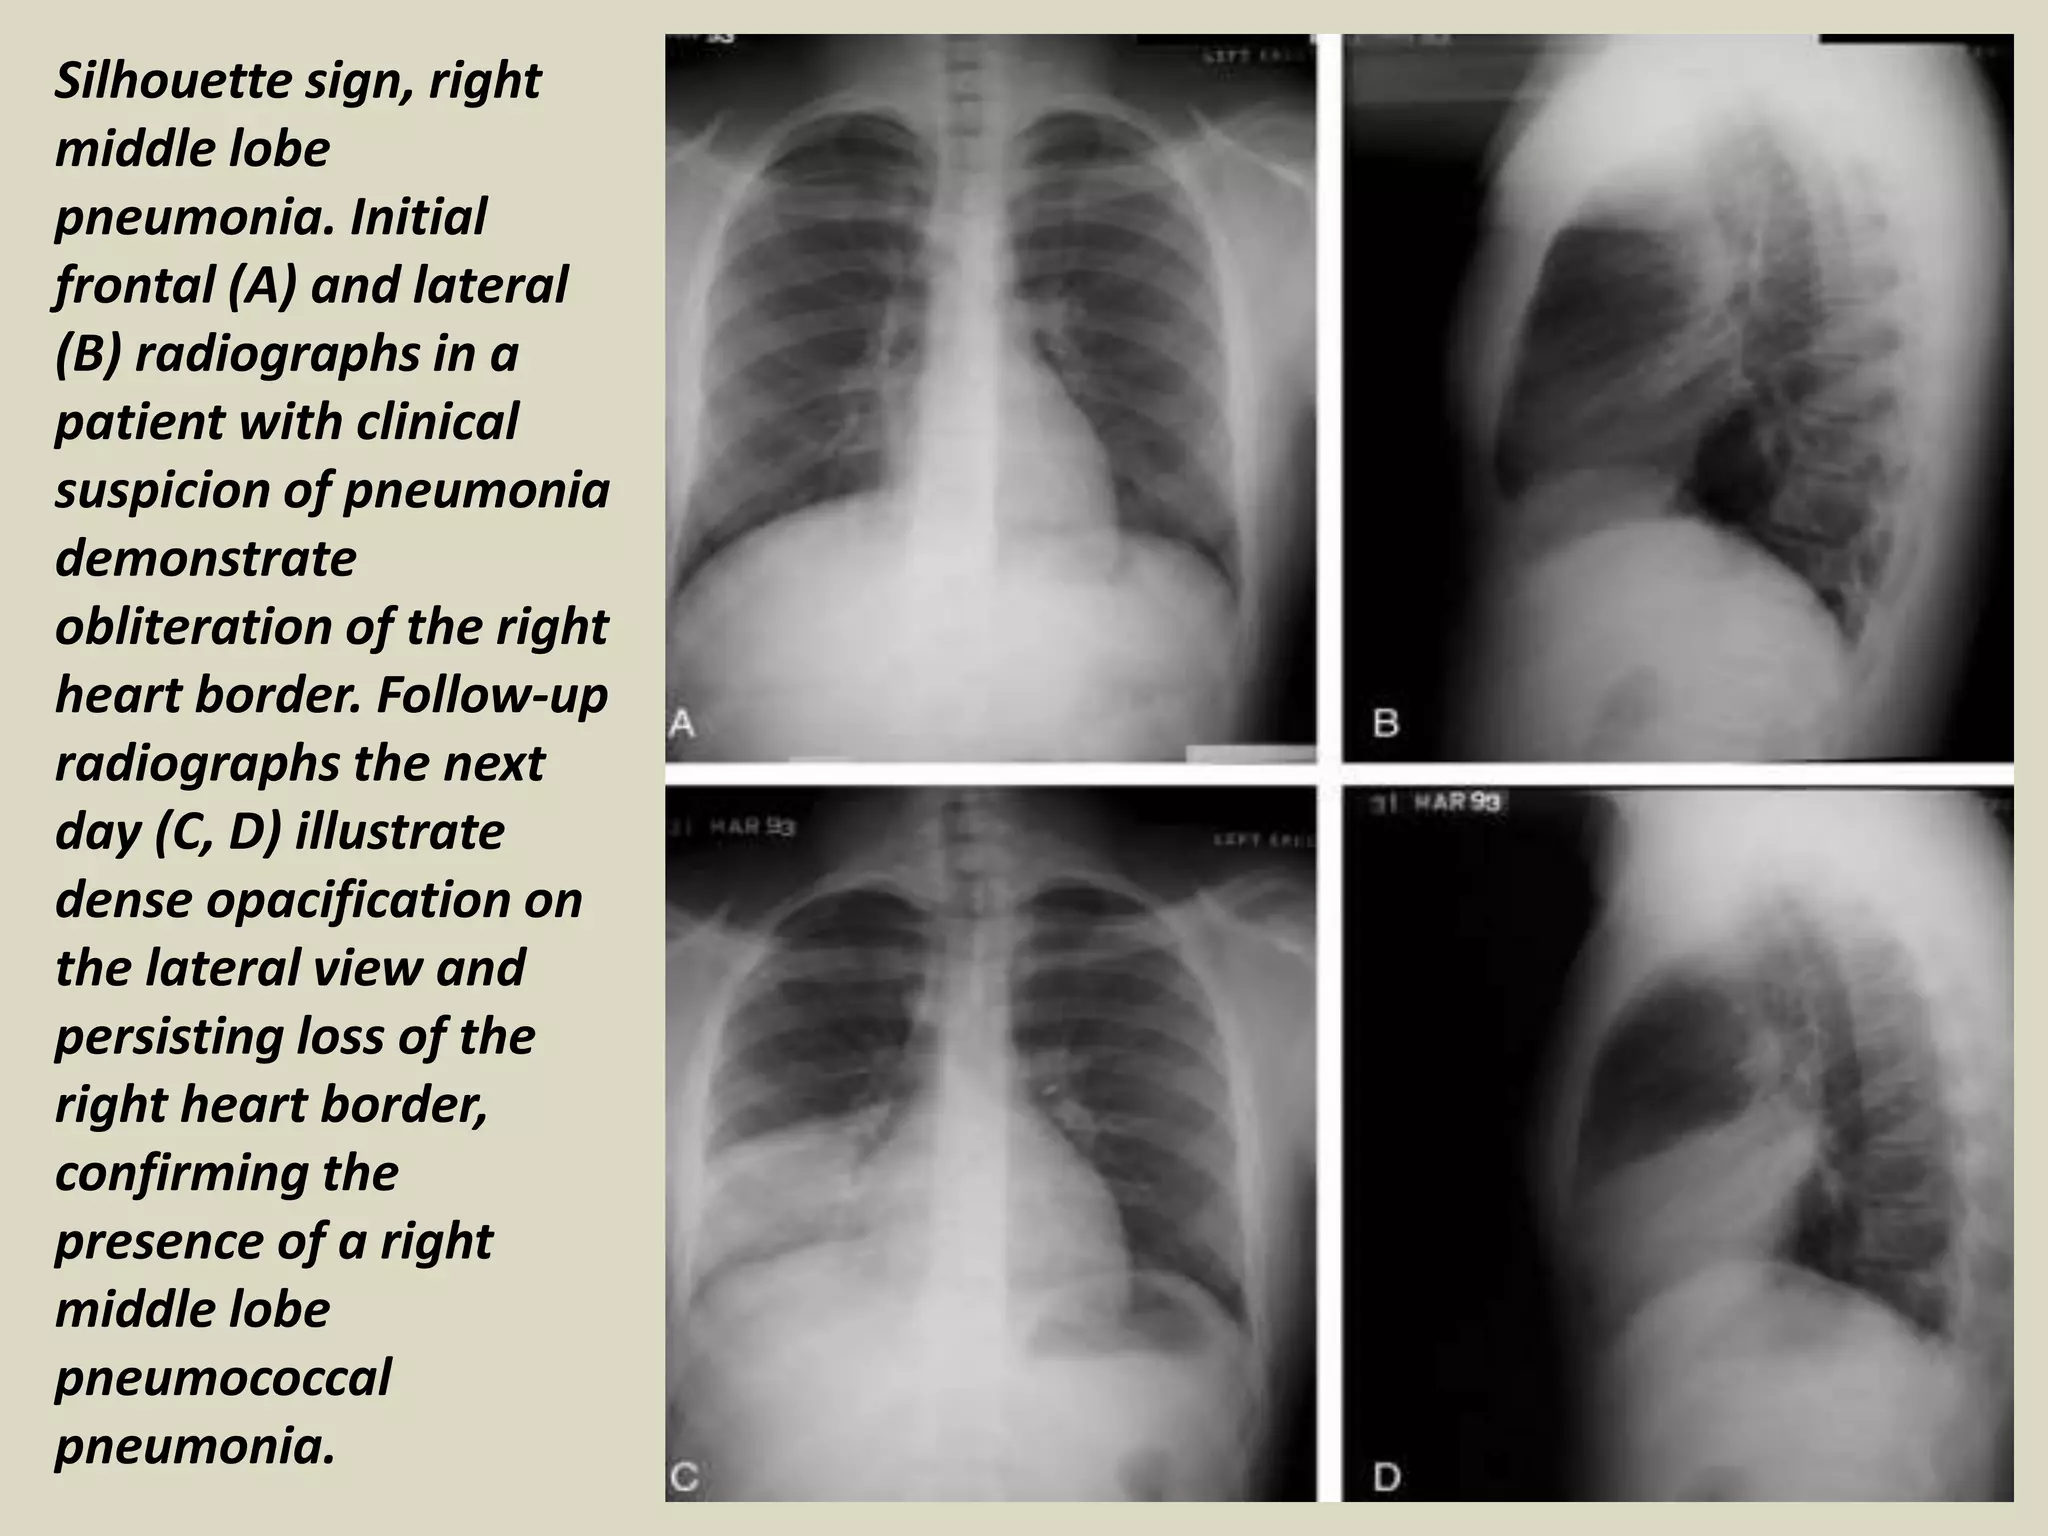

Silhouette sign, right

middle lobe

pneumonia. Initial

frontal (A) and lateral

(B) radiographs in a

patient with clinical

suspicion of pneumonia

demonstrate

obliteration of the right

heart border. Follow-up

radiographs the next

day (C, D) illustrate

dense opacification on

the lateral view and

persisting loss of the

right heart border,

confirming the

presence of a right

pneumococcal

pneumonia.

Silhouette sign, right middlelobe pneumonia. Initial frontal (A) and lateral (B) radiographs in a patient with clinical suspicion of pneumonia demonstrate obliteration of the right heart border. Follow-up radiographs the next day (C, D) illustrate dense opacification on the lateral view and persisting loss of the right heart border, confirming the presence of a right middle lobe pneumococcal pneumonia.